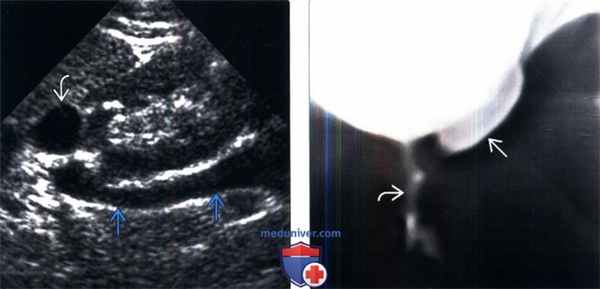

Болюсное введение контрастного вещества и последующее динамическое исследование различных фаз контрастирования способствует четкому выявлению уретероцеле (рис. 3б).

Уретероцеле обнаружено у 3 (8,1%) пациентов из 37. Этот порок уретеровезикального сегмента на МСКТ характеризовался с кистовидным расширением внутрипузырного сегмента мочеточника. При этом отчетливо определяется округлая полость, вдающаяся в просвет мочевого пузыря (рис. 3).

Рис 3. МСКТ картина уретероцеле. Трехмерная реконструкция. Удвоение почек и мочеточника справа (a) и уретероцеле слева (б)